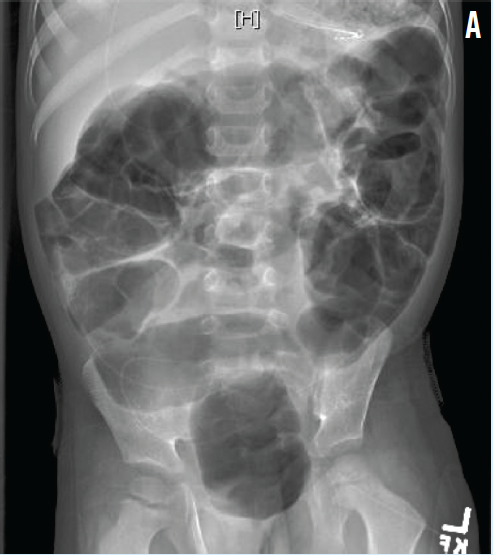

Rotavirus Gastroenteritis Presenting Atypically With Ileus

Melissa Kaori Silva Litao, MD

A 4-year-old boy was transferred to our hospital from another institution for abdominal distention of 1 day’s duration.